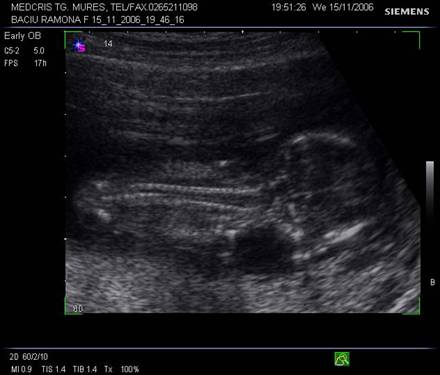

Fig. nr.112 Sarcina 12 saptamani la ecografia transvaginala